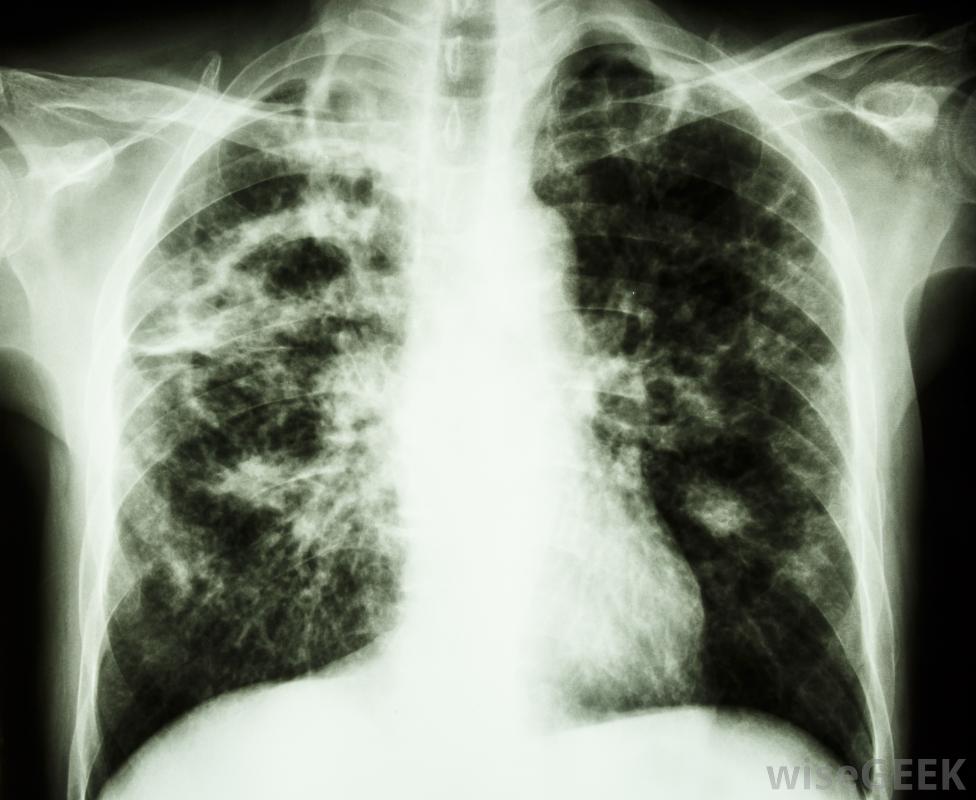

異煙肼是一種治療肺結核的藥物。它也可以用來預防那些接觸過結核病感染者的人。這種抗生素的作用是抑制結核桿菌的生長和繁殖。因為它只能治療活動性結核病感染,患有非活動性感染的人可能需要繼續治療長達一年。胃部的壓痛或疼痛可能是異煙肼的副作用這種藥物通常每天服用一次,喝滿一杯水。除非會引起胃部不適,否則應該空腹服用。異煙肼可以是片劑或膠囊,吞咽困難的患者可以使用糖漿形式。通常,醫生會在這種療法的同時開一種B6維生素來抵消潛在的麻木或刺痛感。酸奶油會與異煙肼相互作用,因此應該避免。當一個人服用異煙肼時,應嚴格避免飲酒,因為它可能更容易造成肝臟損害。某些食物也必須避免或謹慎食用,如人參、巧克力,以及豆制品。熟肉、雞肝和一些乳制品,如酸奶油和酸奶,也會與異煙肼相互作用鱷梨,香蕉,葡萄干,以及許多類型的奶酪,如馬蘇里拉奶酪,美式奶酪和切達奶酪都應該受到限制。所有的咖啡因,酸菜,食用無花果也應格外小心。異煙肼的副作用可能包括腺體腫脹服用異煙肼時食用這些食物可能會導致相互作用。這可能導致嘔吐、惡心和腹瀉。也可能發生胸痛、心跳不規則和潮紅。一些患者報告嚴重頭痛、潮紅和頸部僵硬。如果患者出現這些癥狀,必須立即就醫服用異煙肼的患者應定期進行血液檢查,以確保肝臟功能正常患者還應注意異煙肼可能產生的其他副作用。這些副作用包括眼睛疼痛和其他視力問題、發燒、胃部壓痛、皮疹、腺體腫大,可能會出現喉嚨痛、四肢麻木或刺痛。出現這些癥狀的人應立即聯系醫生。異煙肼用于幫助清除活動性結核病感染異煙肼也可能與某些實驗室檢查相互作用,如尿糖試驗。對乙酰氨基酚、抗真菌藥物和苯妥英鈉也可能與異煙肼相互作用。患者應在使用前與處方醫生討論所有其他藥物和補充劑截至2011年,沒有足夠證據表明服用該藥對未出生或哺乳期嬰兒的潛在風險。如果患者懷孕,應立即通知醫生。此外,患有肝臟或腎臟疾病、糖尿病或人類免疫缺陷病毒(HIV)的患者可能需要調整該藥物的劑量。異煙肼的副作用可能包括嚴重頭痛。